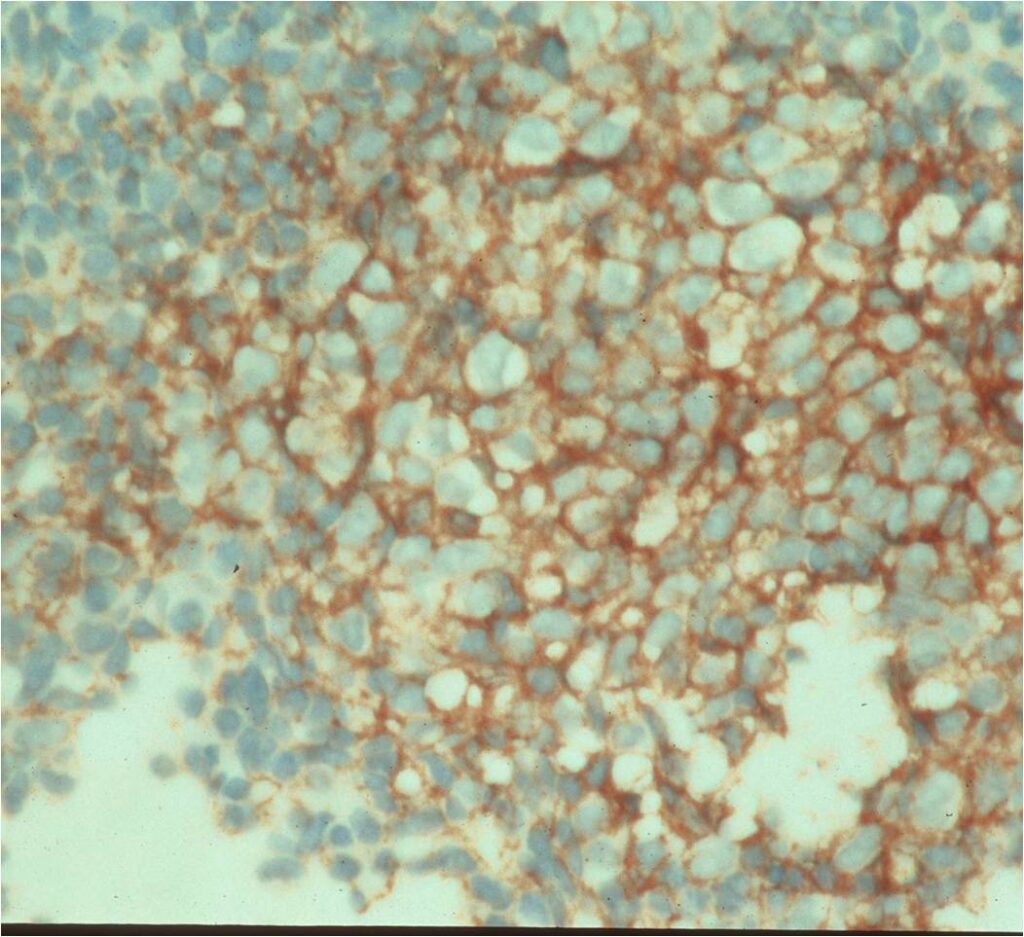

- Ewing sarcoma is composed of undifferentiated, small round, polygonal mesenchymal cells rich in glycogen

- Sheets of uniform cells with scanty pale cytoplasm and indistinct cell boarders

- No Matrix

- Nuclei are round/oval with finely dispersed chromatin

- Virtually no cytoplasm

- Areas of necrosis

- Variable number of mitoses

- Cells are similar in appearance

- Geographic necrosis with perivascular sparing

- PAS (glycogen positive); Reticulin stain poor

- Immunostains: Vimentin (+), CD99 (+); Leukocyte Antigen Negative

- Overexpress MIC2 detected by CD99

Small Round Blue Cells No Matrix Large Nuclei No Cytoplasm